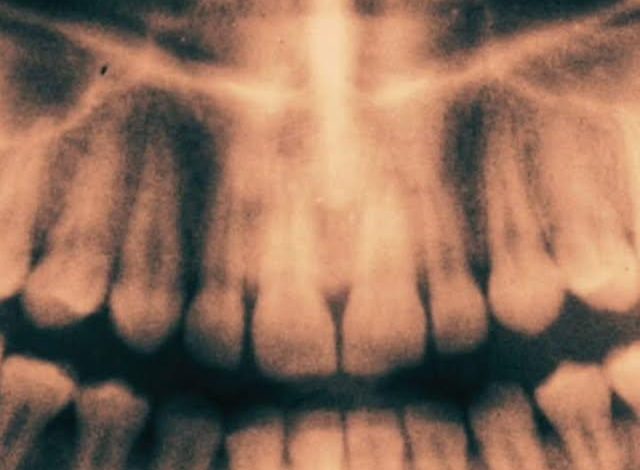

Pesquisadores da Universidade do País Basco descobriram que a polpa dos dentes do siso contém um tipo raro de célula-tronco capaz de regenerar ossos, neurônios e tecidos cardíacos. Em testes, essas células demonstraram atividade elétrica semelhante à de neurônios humanos e melhoraram a função cardíaca e regeneraram cartilagens em camundongos. Os dentes do siso, geralmente extraídos entre os 15 e 25 anos, possuem células jovens com potencial terapêutico. Com cerca de 10 milhões de extrações anuais no mundo, biobancos como a Stemodontics poderiam armazenar esses dentes como uma fonte de células-tronco compatíveis para uso futuro, sem risco de rejeição. Uma descoberta revolucionária para a medicina regenerativa. Fonte: